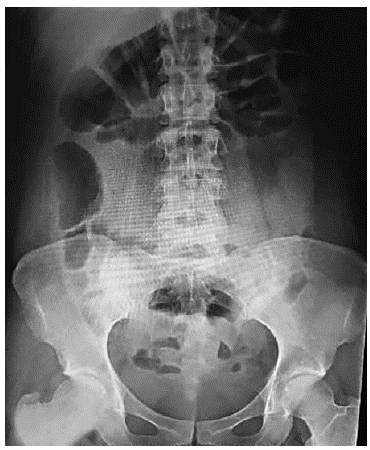

A 29 year-old female without significant clinical histories besides an appendectomy, presents with a clinical picture of 8 hours of moderate generalized abdominal pain following a programmed colonoscopic 12mm sigmoidal polyp resection. At presentation the patient denied vomiting or fever, physical examination showed generalized abdominal pain without rebound tenderness or signs of peritoneal irritation along with mild distention. Vital signs showed a 115/70 mmHg blood pressure, 75 bpm heart rate, 37.1 degrees Celsius, temperature and 92% oxygen saturation. Blood work showed normal renal function, coagulation and electrolytes, with significant leukocytosis of 24.830, neutrophils 90,9% along with a C-Reac-tive Protein of 124 mg/L and normal hemoglobin levels. Arterial blood gases showed no acid-base abnormalities or elevated levels of lactate. The patient was first seen by the emergency medical team, which ordered chest and abdominal x-rays that exhibited no signs of intestinal obstruction or pneumoperitoneum. (Figure 1 and 2).